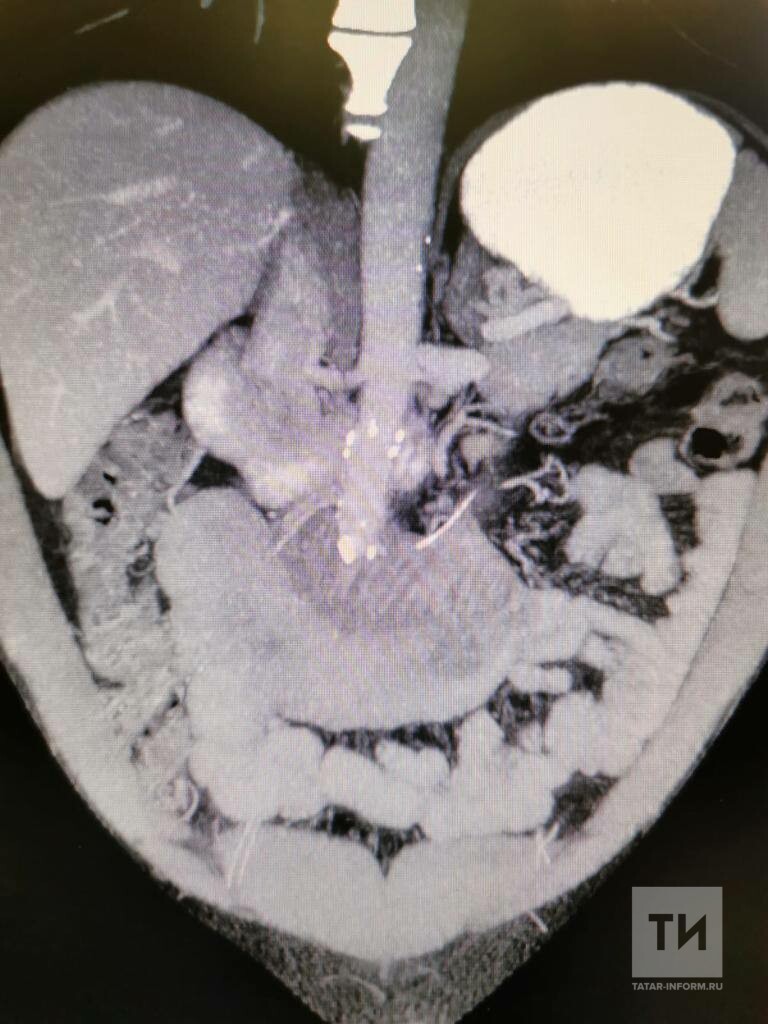

В РКБ мужчине сделали МРТ и забрали на операцию – как выяснилось, кость проткнула кишечник и вышла в брюшную полость.

Фото: Пресс-служба РКБ Татарстана

«Хирурги аккуратно удалили кость, зашили кишечник и перевели пациента в палату. Через несколько дней мужчину в удовлетворительном состоянии выписали домой», – рассказали агентстсву в пресс-службе РКБ.